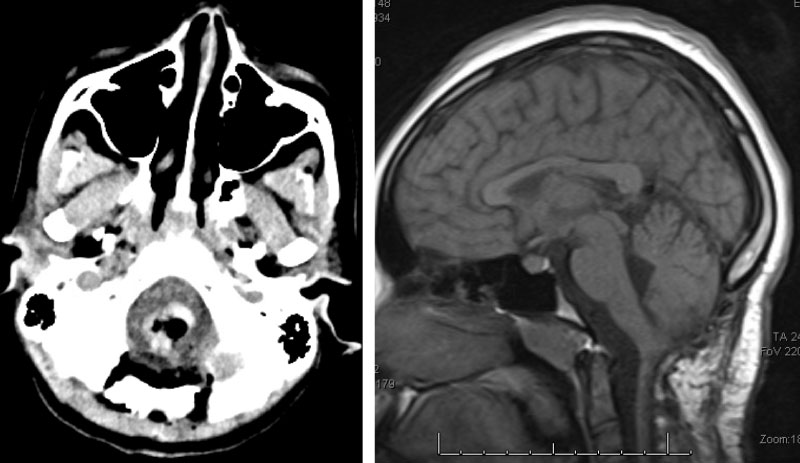

Following, the intramedullary brainstem tumor was successfully resected via suboccipital craniotomy and upper cervical laminectomy. The patient did well after surgery.

Figure 3. Immediate post-op CT (left) and two-year follow-up MRI (right).